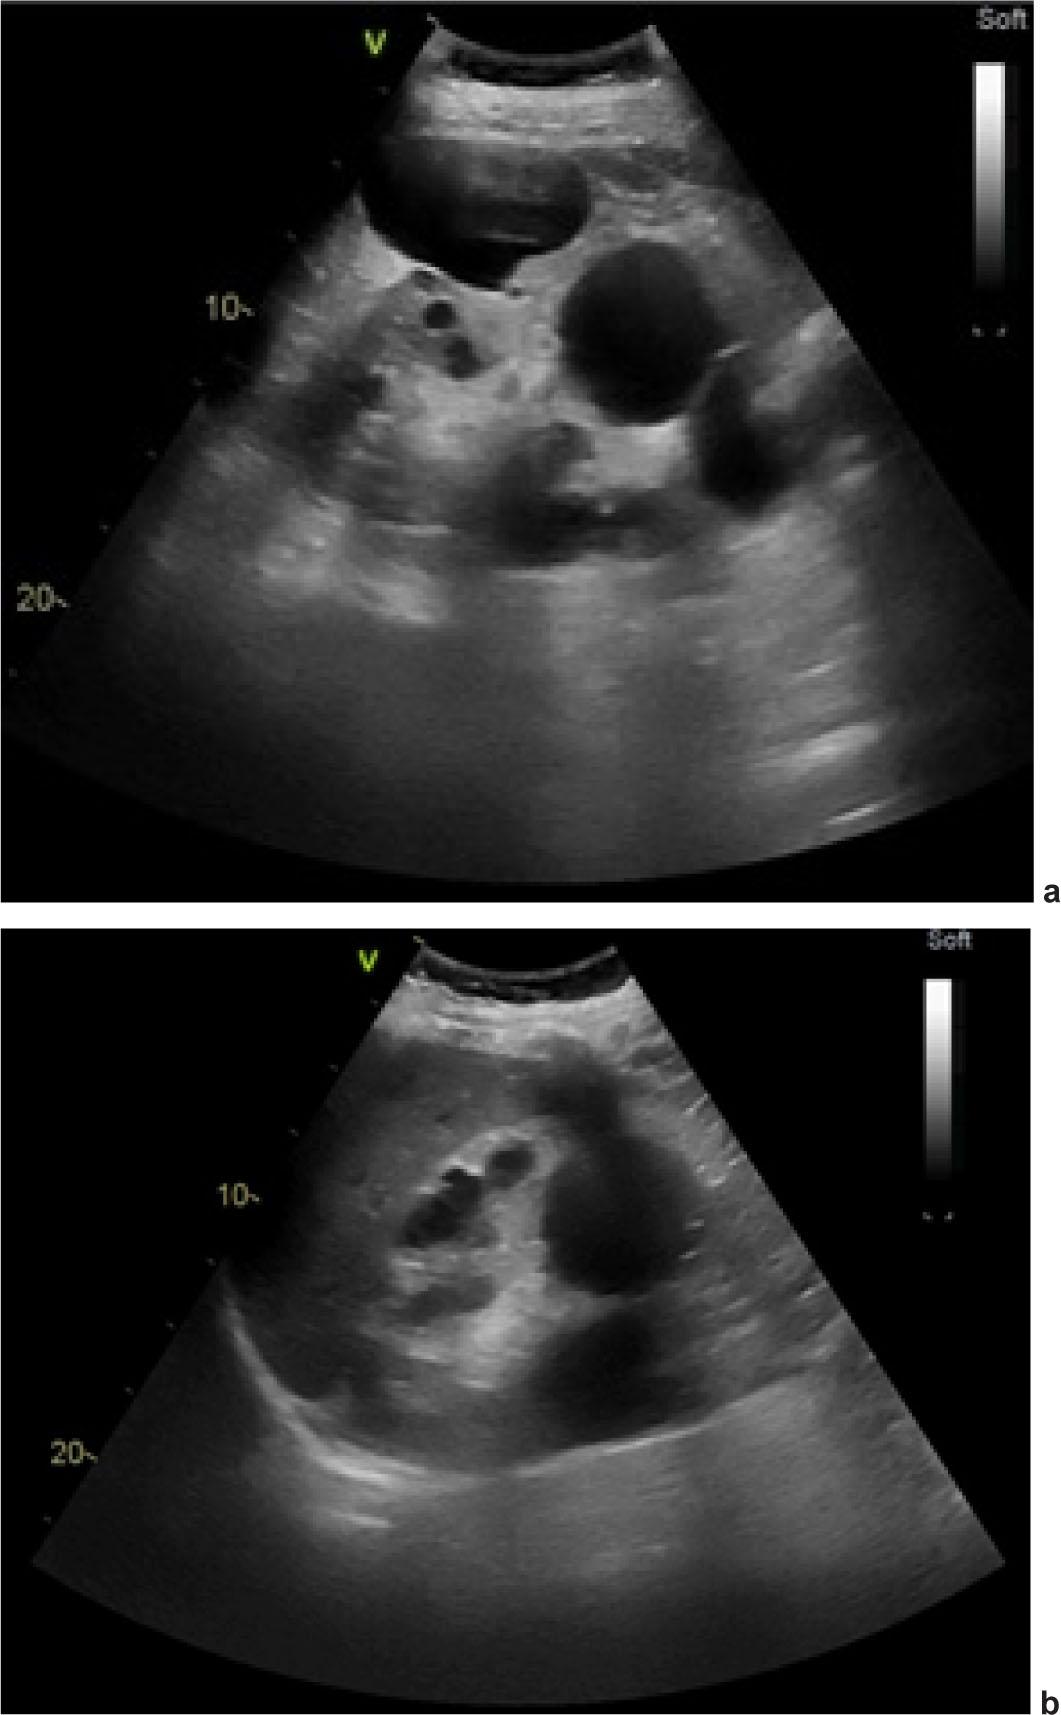

Arterial O2 pressure level was normal, erythropoietin level was slightly increased (Table 1), and Janus Kinase (JAK) 2 V617F mutation was absent. Abdominal echography (Figure 3A–B) showed enlarged kidneys (right kidney 20/12 cm, left kidney 16/11 cm), containing several round-oval formations with a clear contour, transonic content, some confluent, most likely renal cysts. At the level of the left kidney, 12 cystic images were visualized, the largest 6/3 cm. At the level of the left kidney, 8 cystic images, the largest 5/5 cm, were visualized. The presence of more than three renal cysts bilaterally is highly suggestive of polycystic kidney disease (PKD).

Abdominal ultrasound showing bilateral polycystic kidney disease: (a) Right kidney; (b) Left kidney